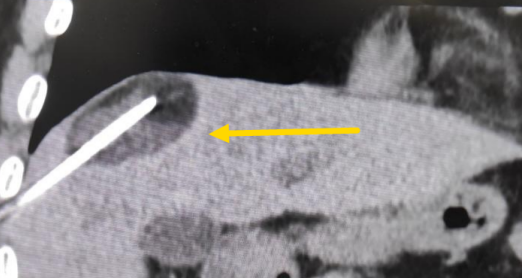

經(jīng)過(guò)多學(xué)科討論,陳寶瑩主任根據(jù)影像資料指出,患者轉(zhuǎn)移瘤位于腹膜后,內(nèi)側(cè)瀕臨人體最大的血管——主動(dòng)脈;前方同樣有血管緊貼腫瘤;外側(cè)是腎臟,后方是椎體和神經(jīng),夾縫中進(jìn)針難度大,治療時(shí)要避免周?chē)匾K器、血管和神經(jīng)的損傷,因此可以選擇CT引導(dǎo)下精準(zhǔn)穿刺活檢同步冷凍消融治療,即獲得病理組織有利于下一步全身治療方案的調(diào)整,同時(shí)殺死腹膜后轉(zhuǎn)移瘤,周?chē)=M織損傷的可能性也小。

術(shù)中陳寶瑩主任、李鐵柱教授、兀云飛醫(yī)生、魏東紅技師、汝平護(hù)士協(xié)調(diào)配合,夾縫進(jìn)針難度雖大,但在CT引導(dǎo)下逐步進(jìn)針,精準(zhǔn)到位,順利活檢取得組織,由于腫瘤較大,為了提高消融效率,平行置入兩根冷凍消融針,同時(shí)啟動(dòng)冷凍消融,術(shù)中清晰觀察到冰球完全覆蓋病變,患者沒(méi)有任何不舒服,治療中還可以和醫(yī)生聊天。